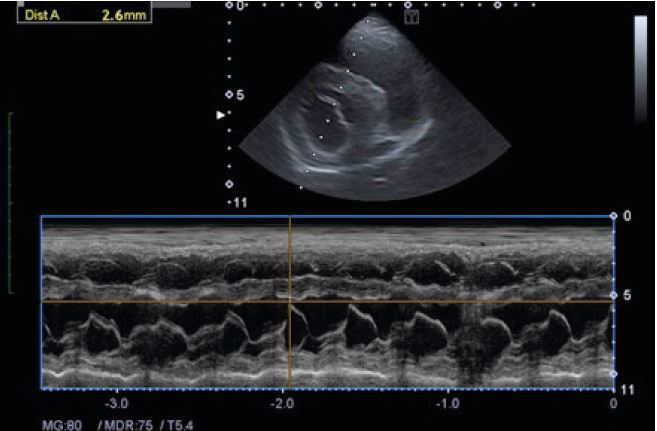

Кардіологічне дослідження у собаки в імпульснохвильовому

доплерівському режимі, що відображає аортальний потік.

Обстеження серця в режимі 2D. Джерело: Клініка Альянс

Дослідження серця в 2D М-режимі з візуалізацією аорти та лівого передсердя. Джерело: Клініка Альянс.